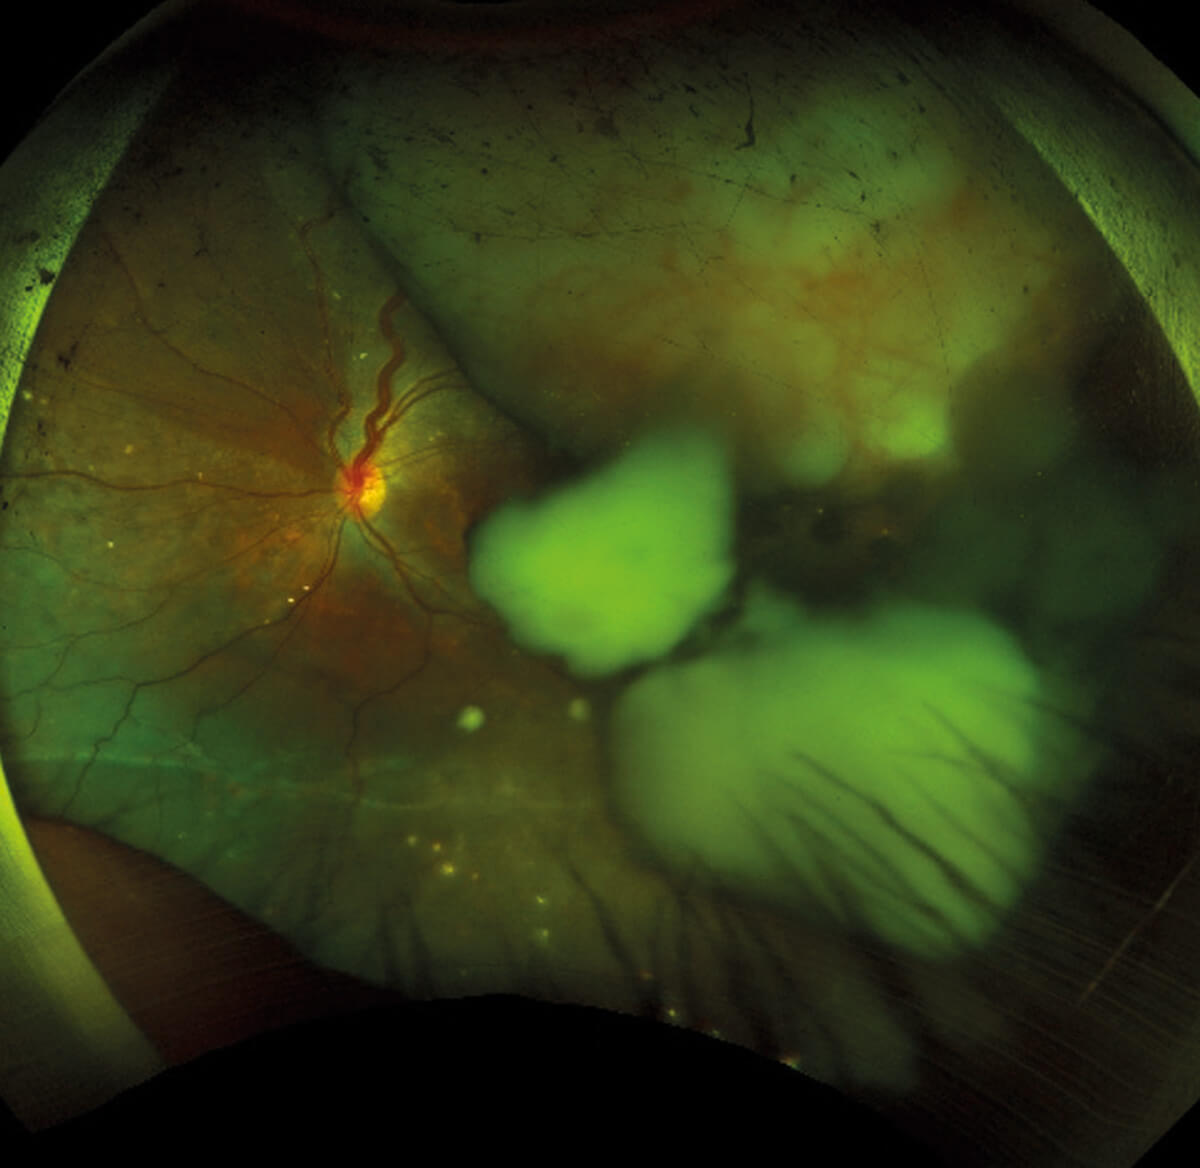

Figure 1: Large mass in the superior-temporal quadrant of the left eye,

accompanied by retinal detachment and feeder vessels.

A 29-year-old woman with a family history of Rb presented with floaters in her left eye. Her son had previously been diagnosed with bilateral Rb but passed away due to metastatic disease at a young age. On examination, a large mass was observed in the superior-temporal quadrant of the left eye (Figure 1), accompanied by retinal detachment and feeder vessels - classic signs of Rb. Participants were asked how they would manage this case. The options and results were: